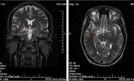

Glejak, podobnie jak inne guzy mózgu, nie powoduje charakterystycznych objawów. Rozwijając się w danej lokalizacji, uszkadza komórki obszarów odpowiedzialnych za konkretne aktywności. Może to doprowadzić na przykład do niespodziewanych zmian zachowania. – Zdarza...